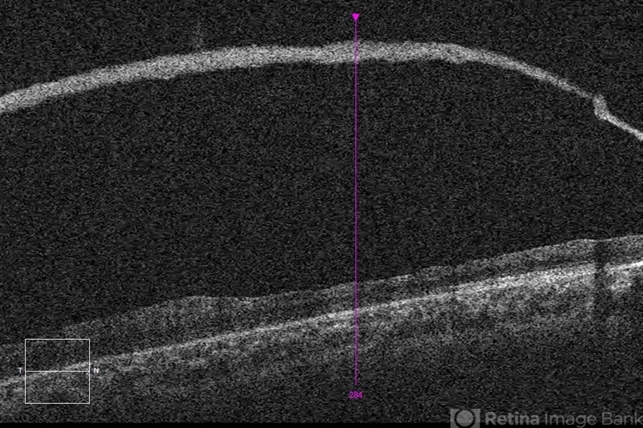

- retinoschisis, retinal hole

- Imaging device

Optical coherence tomography system

Zeiss Cirrus 5000 - Description

- 21-year-old male with congenital retinoschisis with bilateral macular involvement & large inner retinal hole OD.